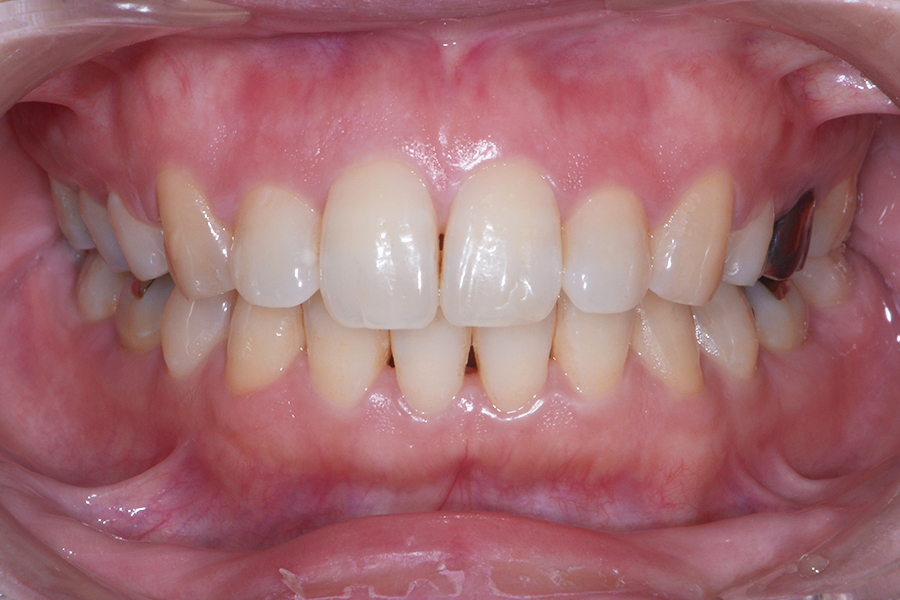

【30代女性】

引っ込んでいる部分を治したい

【矯正歯科治療】

- 担当医

- 三留先生

- 主訴

- 引っ込んでいる部分を治したい

- 期間

- 7か月

- 費用

- 治療費30万+30万(別途調整料)

- 治療内容

- 上下顎リンガル矯正(裏側矯正)

- 治療に伴うリスク

- 後戻り